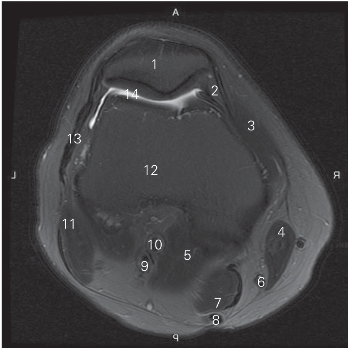

图5-24 经髌骨的横断层MR T2WI FS

1 髌骨 patella 2 髌内侧支持带 medial patellar retinaculum

3 股内侧肌 vastus medialis 4 缝匠肌 sartorium

5 腓肠肌内侧头 medial head of grastrocnemius

6 股薄肌腱 gracilis tendon 7 半膜肌 semimembranosus

8 半腱肌腱 simitendinosus tendon

9 胫神经 tibial nerve 10 腘动、静脉 popliteal artery and vein

11 股二头肌 biceps femoris 12 股骨 femur

13 髂胫束 iliotibial tract 14 膝关节腔 cavity of knee joint